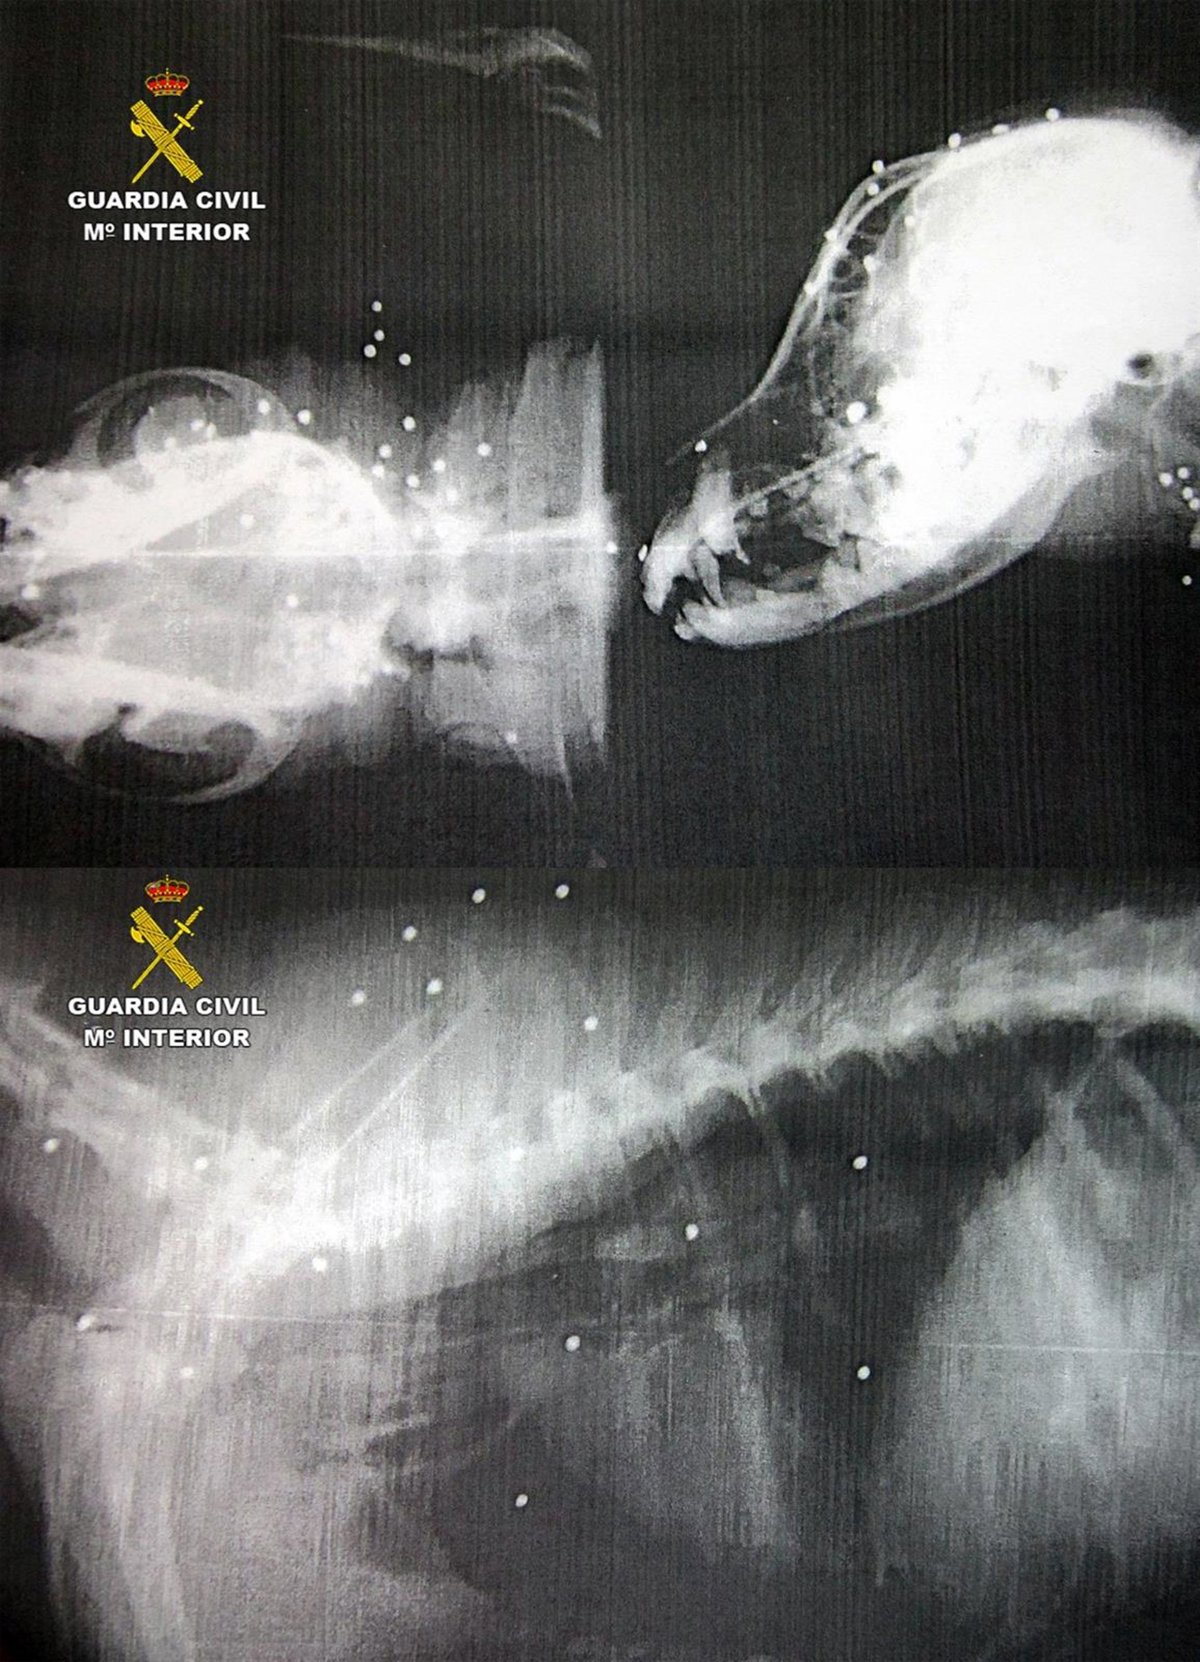

Radiografías de los perros disparados

GUARDIA CIVIL

Uno de los canes tuvo que ser atendido en un hospital veterinario de Murcia, donde quedó ingresado debido a la gravedad de las heridas causadas por el impacto de 58 perdigones -pequeños proyectiles de plomo con forma redondeada que contienen los cartuchos-. Los proyectiles le provocaron múltiples heridas y la pérdida de visión en uno de sus ojos. El otro perro alcanzado por un disparo, un cachorro de unos meses, presentaba heridas en el hocico, pero de carácter menos grave que el anterior.